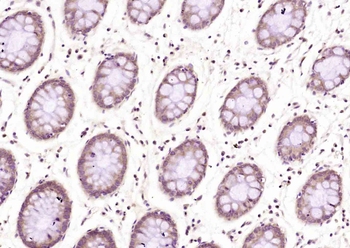

TRIM24 Rabbit Polyclonal Antibody

IF, IHC-Fr, IHC-P

应用稀释比例:IHC-P=1:100-500, IHC-F=1:100-500, IF=1:100-500